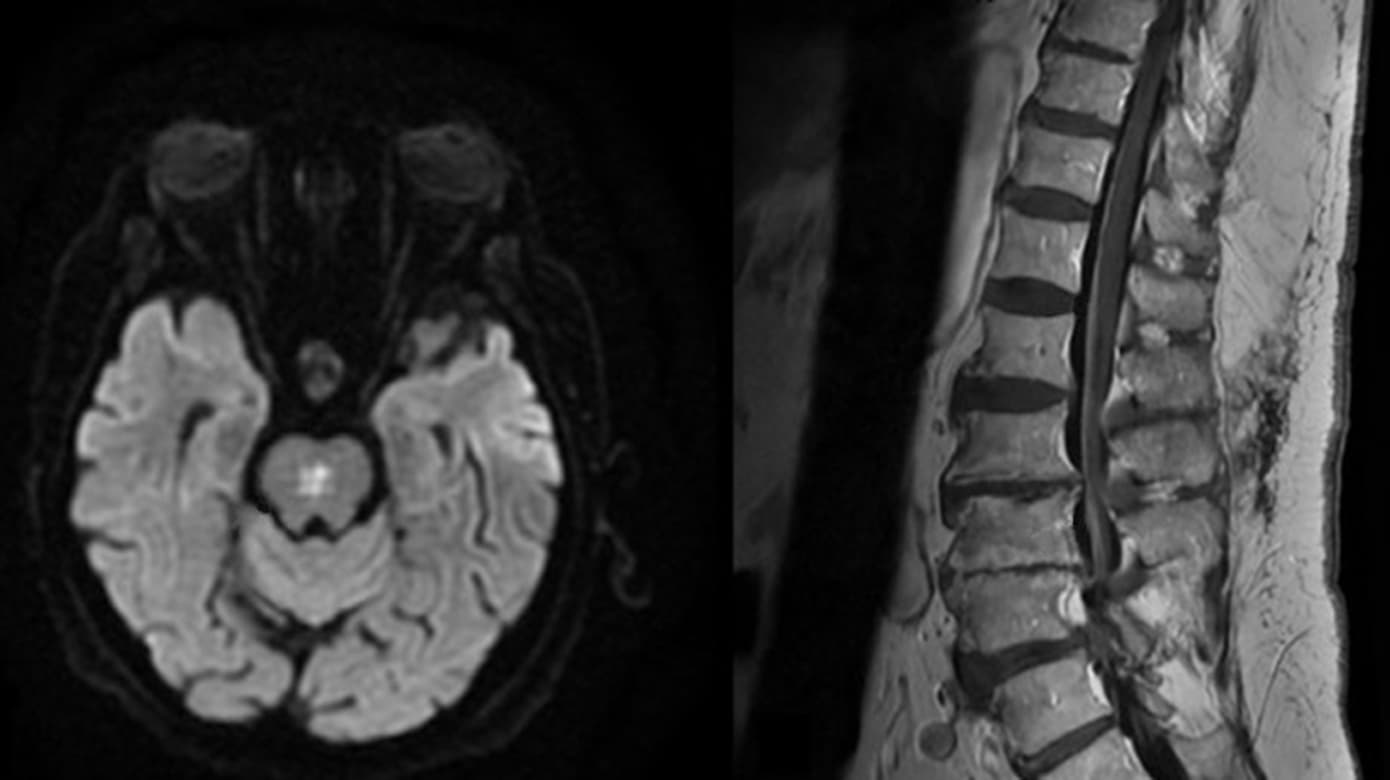

Patienten udviklede hurtigt slap tetraplegi og forblev komatøs. En MR-skanning af hjernen viste en inflammatorisk forandring i pons (Figur 1 A). En nerveledningsundersøgelse viste betydeligt tab af motoriske forhornsceller, og en MR-skanning af ryggen var med kontrastopladning langs de ventrale nerverødder (Figur 1 B). Fundene var forenelige med WNV-induceret encefalomyeloradikulitis.